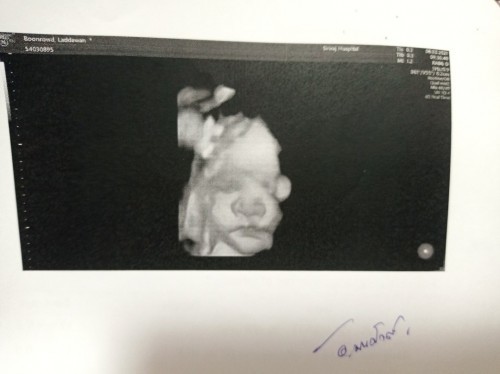

ซาวด์ตอน 24 สัปดาห์ หมอบอกเป็นผู้ชาย 70% คุณปู่เฮลั่นบ้าน แต่มาซาวด์อีกครั้งตอน 32 สัปดาห์ หนูกลายเป็นผู้หญิงไปซะแล้ว คุณยายกรีดลั่นบ้านเลยทีนี้😄😄😄แต่ม่าม๊ากับปะป๋านี่สิ เตรียมของให้หนูแบบผู้ชายซะส่วนใหญ่เลยเนี่ย😅😅😅 คนที่หน้าหงอยที่สุดคงเป็นคุณลุงของหนูเนี่ยแหล่ะ หมายมั่นปั้นมือจะให้เป็นนักยิงปืน สงสัยต้องเปลี่ยนเป้าหมายแล้วล่ะนะคุณลุง🤣🤣🤣🤣#แม่อยากเจอหนูแย้วนะหมวยน้อย